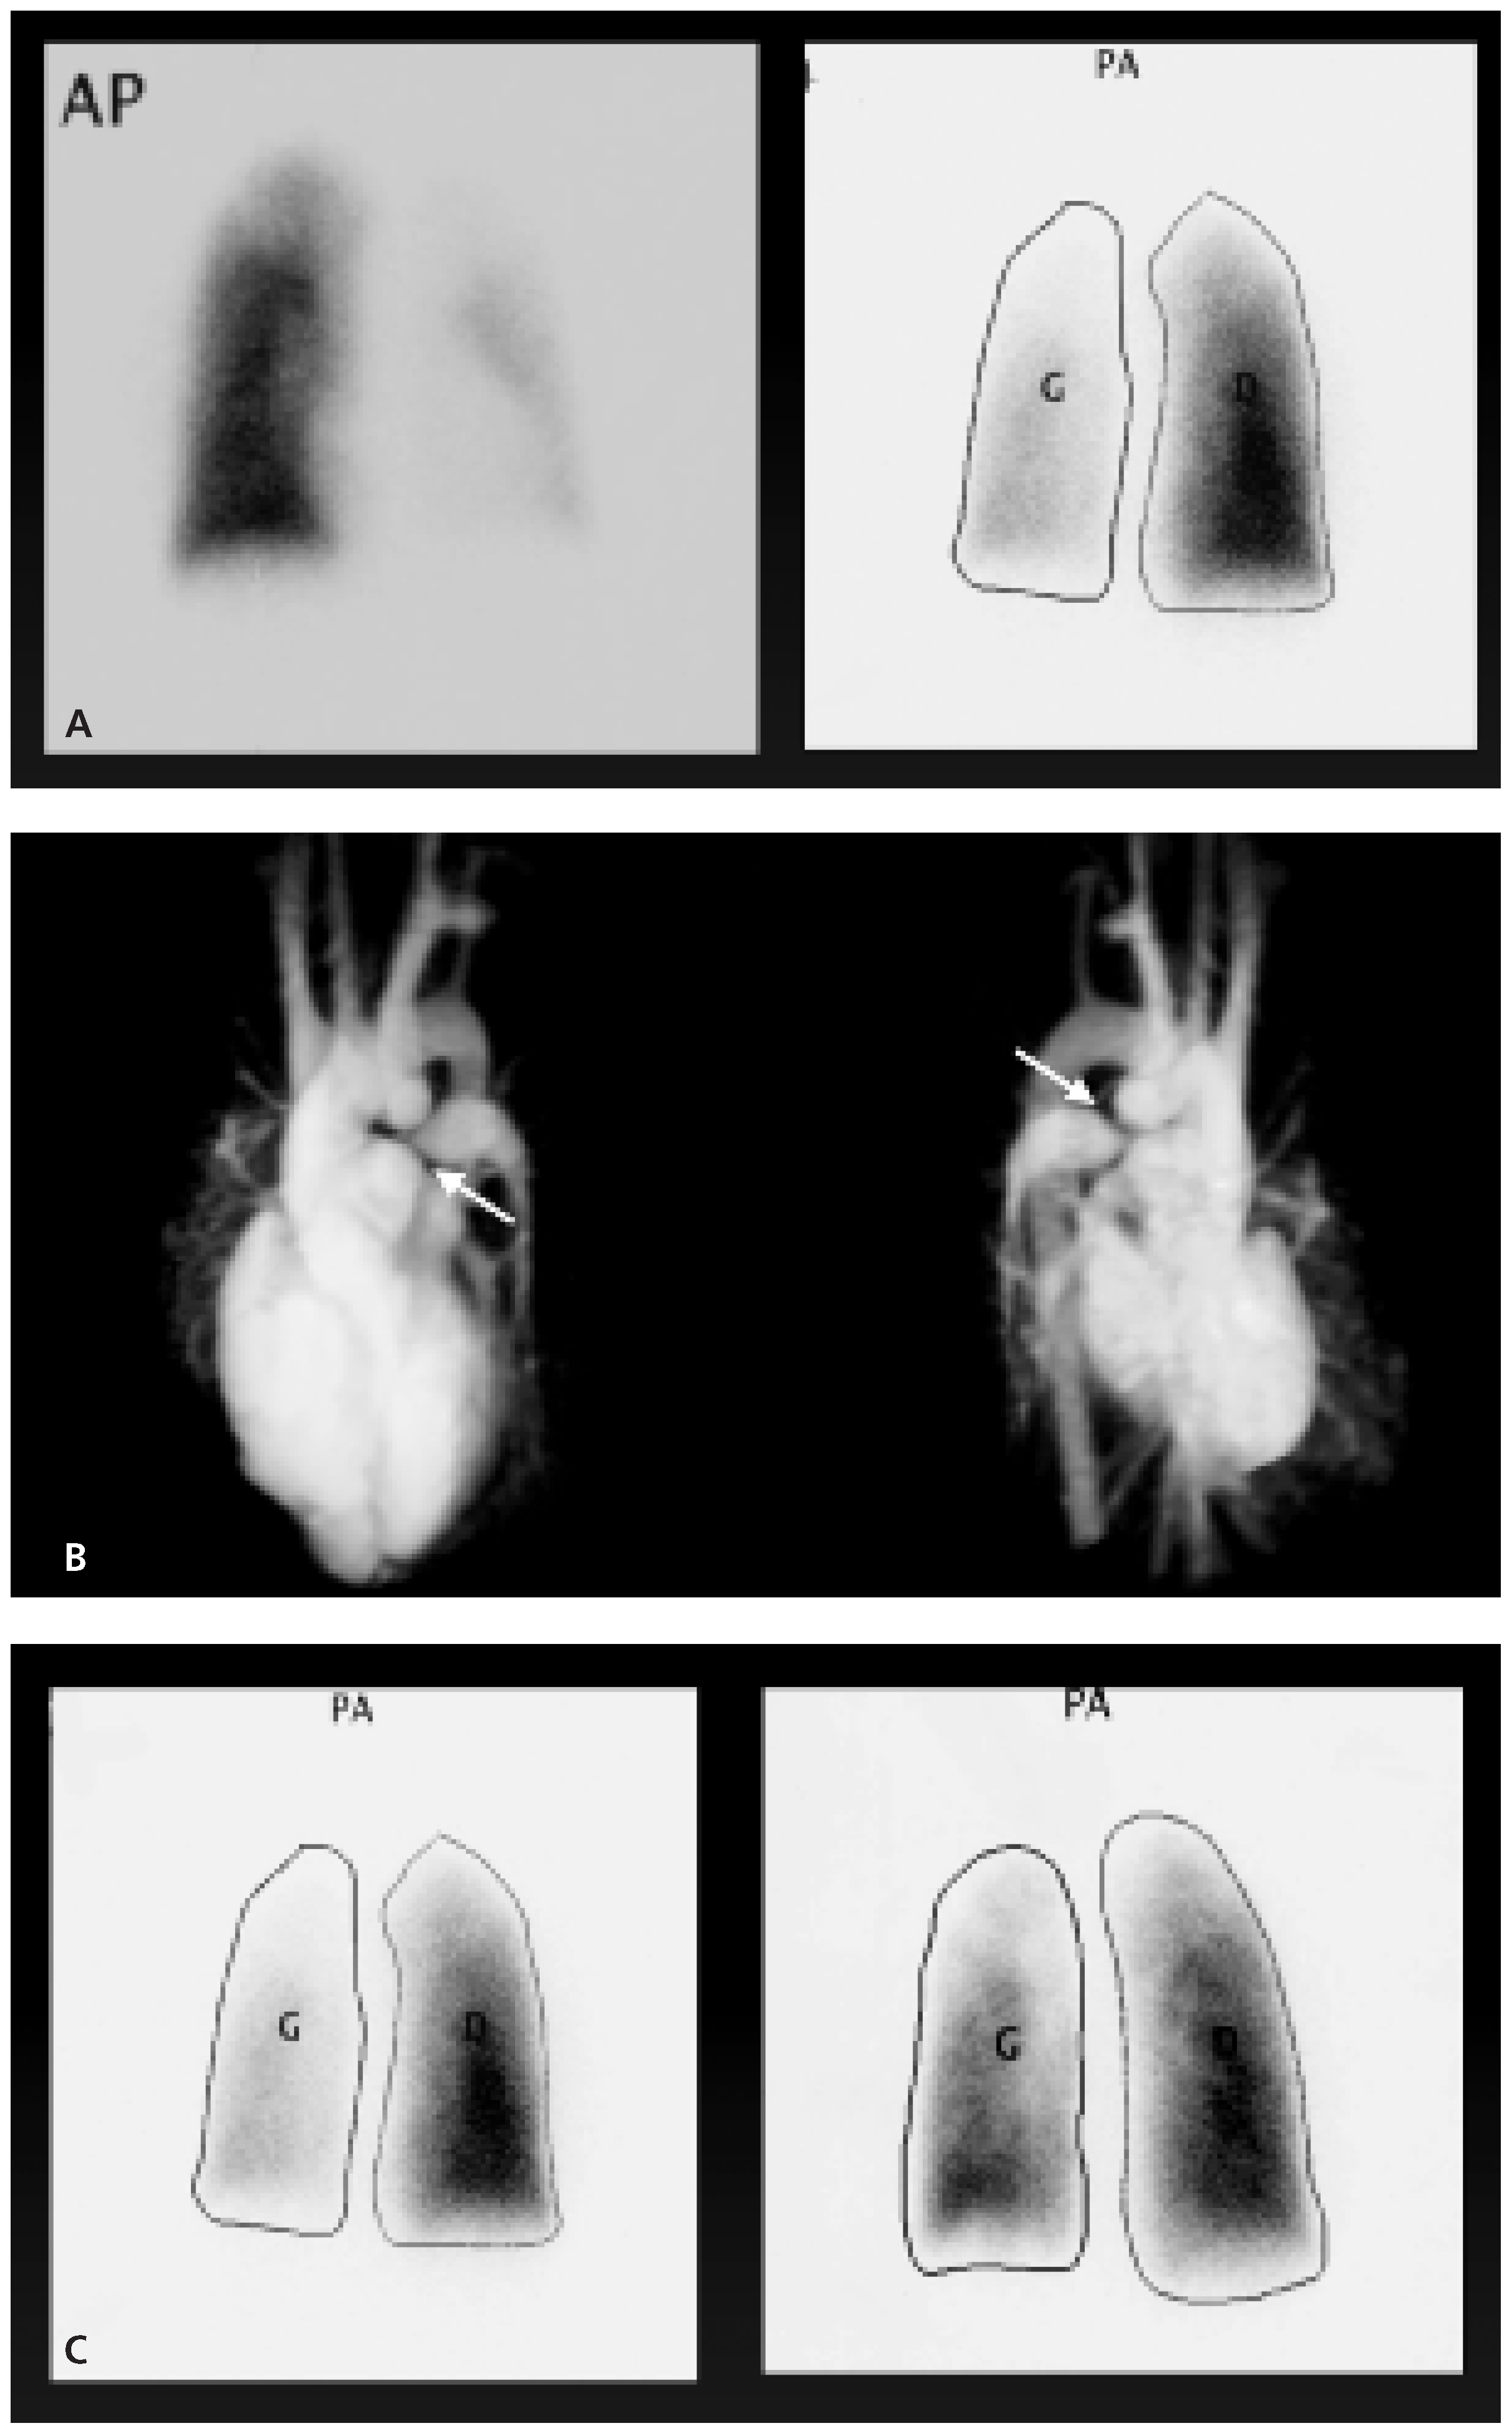

- Pulmonary regurgitation

- Carvalho, J.S.; Shinebourne, E.A.; Busst, C.; et al. Exercise capacity after complete repair of tetralogy of Fallot: Deleterious effects of residual pulmonary regurgitation. Heart 1992, 67, 470–473. [Google Scholar] [CrossRef]

- Therrien, J.; Siu, S.; McLaughlin, P.R.; et al. Pulmonary valve replacement in adults late after repair of tetralogy of Fallot: Are we operating too late? J Am Coll Cardiol. 2000, 36, 1670–1675. [Google Scholar] [CrossRef]

- Vliegen, H.W.; van Straten, A.; de Roos, A.; et al. Magnetic resonance imaging to assess the hemodynamic effects of pulmonary valve replacement in adults late after repair of tetralogy of Fallot. Circulation 2002, 106, 1703–1707. [Google Scholar] [CrossRef]

- Therrien, J.; et al. Optimal timing for pulmonary valve replacement in adults after tetralogy of Fallot repair. Am J Cardiol. 2005, 95, 779–782. [Google Scholar] [CrossRef]